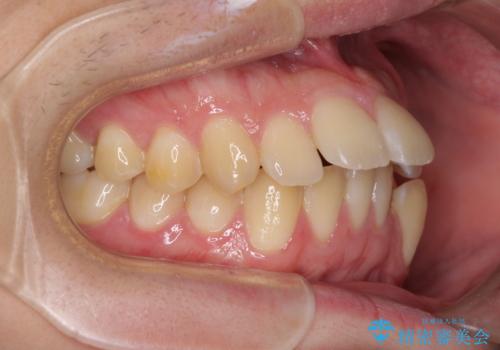

下顎骨が左側に大きく変位しているため、上下の正中位置は極力一致するところをゴールとしました。

上下顎で左右差の大きい抜歯矯正を裏側装置で行ったため、非常に時間がかかりましたが、正中位置も良い位置に改善され、気になっていた突出感も解消されました。